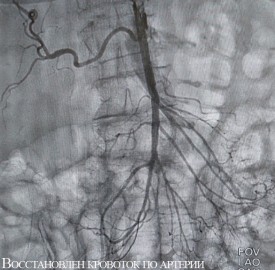

Обеим женщинам было выполнено эндоваскулярное вмешательство — без разрезов, через прокол в бедренную артерию в паху был введен зонд, с помощью которого врачи удалили тромбы из просветов сосудов. Обе пациентки были в сознании во время операции, и прямо на операционном столе у них прошел болевой синдром.

Оперировал обеих больных эндоваскулярный хирург Нарек Вачаганович Марукян. Первая пациентка была выписана на третий день после лечения. Перед этим ей выполнили коронарографию (поскольку поступила она с подозрением на инфаркт), при этом вмешательство на сосудах сердца не потребовалось. Вторую больную выписали на амбулаторное лечение через неделю после операции.